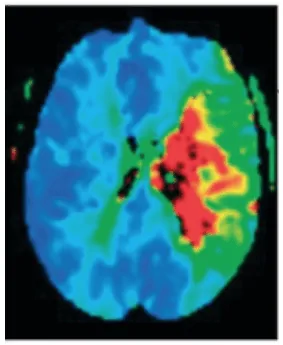

تقنيات التصوير العصبي، مثل التصوير بالرنين المغناطيسي للدماغ، تسمح بتأكيد وتحديد تضاريس الإصابة، مما يجعلها ذات فائدة كبيرة في مقاربة المرض. في المرحلة الحادة يمكن تحديد النسيج المتعرض للاحتشاء بفضل تسلسلات الانتشار، وكذلك تقدير حجم النسيج عبر تسلسلات التروية (Ustrell-Roig y Serena Leal, 2007).

يُستخدم التباين الإيجابي بين حجم الاحتشاء وحجم الهالة (التفاوت) كمؤشر لتنبؤ بالاستجابة الجيدة للعلاج (يشير تفاوت إيجابي إلى وجود هالة كبيرة مقارنة بالمنطقة المحتشية، مما يدل على وجود نسيج دماغي قد يكون قابلاً للإنقاذ). ولذلك، من المهم جداً توافر تقنيات التصوير العصبي التي تسمح بتحديد نواة الاحتشاء ومنطقة الهالة للتنبؤ بتشخيص المريض واستخدامها عند اتخاذ قرارات علاجية لاختيار المرضى الذين قد يستفيدون من علاجات إعادة التروية خارج نوافذ الزمن التقليدية (García et al., 2022) (الشكل 1).